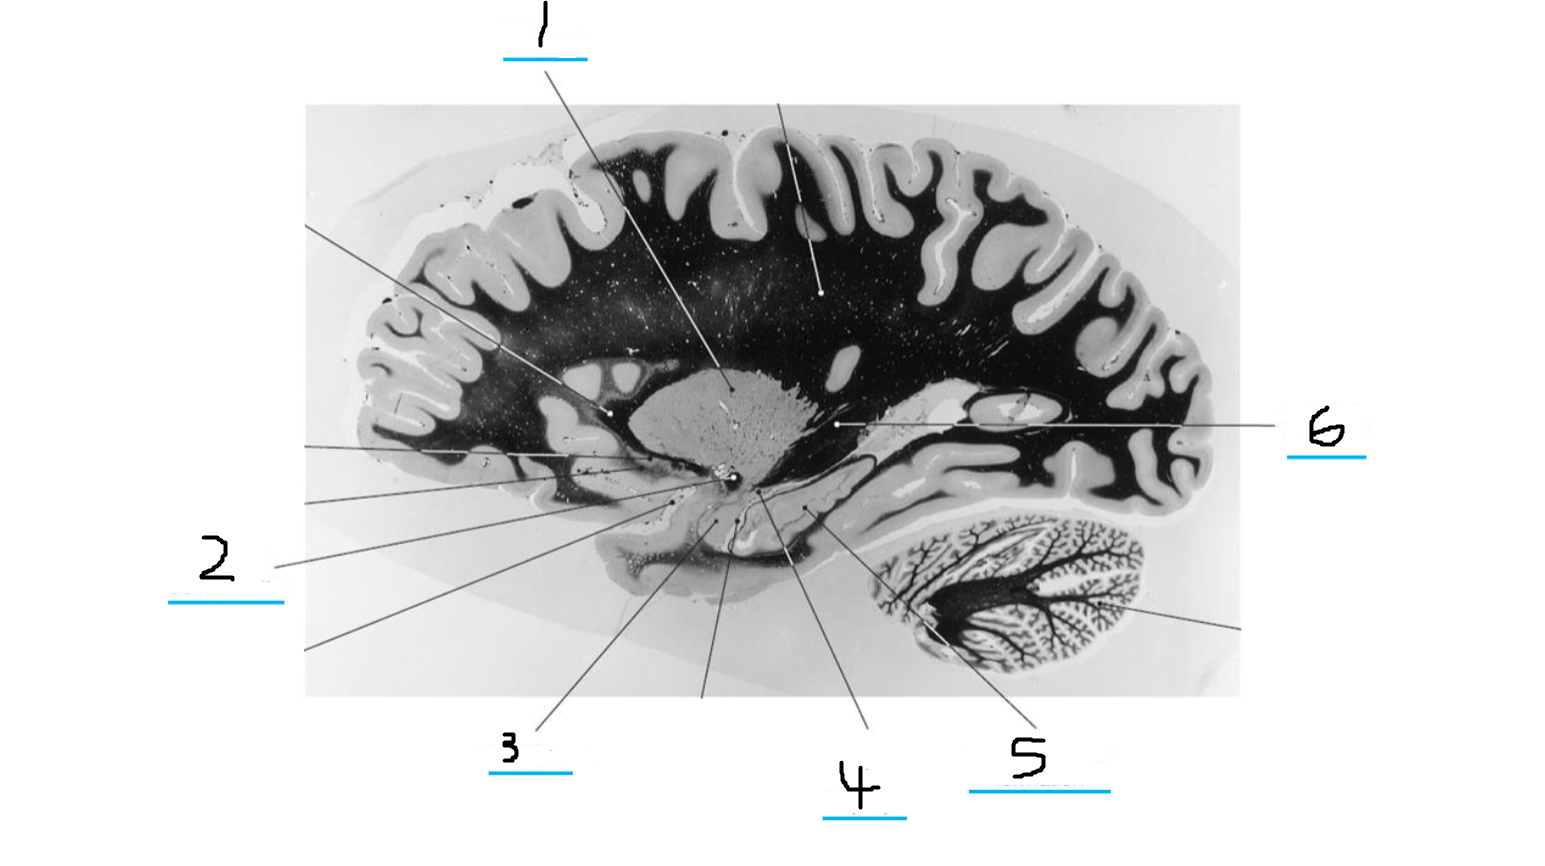

#1 is the:

Fornix

#2 is the:

Caudate

#3 and #14 is the:

Thalamus

#4 is the:

Putamen

#5 is the:

Olive

#6 is the:

Pyramid

#7 is the:

Basilar Pons

#8 is the:

Substantia Nigra

#9 is the:

Crus Cerebri

#10 is the:

Hippocampus

#11 is the:

#12 is the:

Red Nucleus

#13 is the:

Internal Capsule

#15 is the:

Lateral Ventricle

#16 is the:

Corpus Callosum